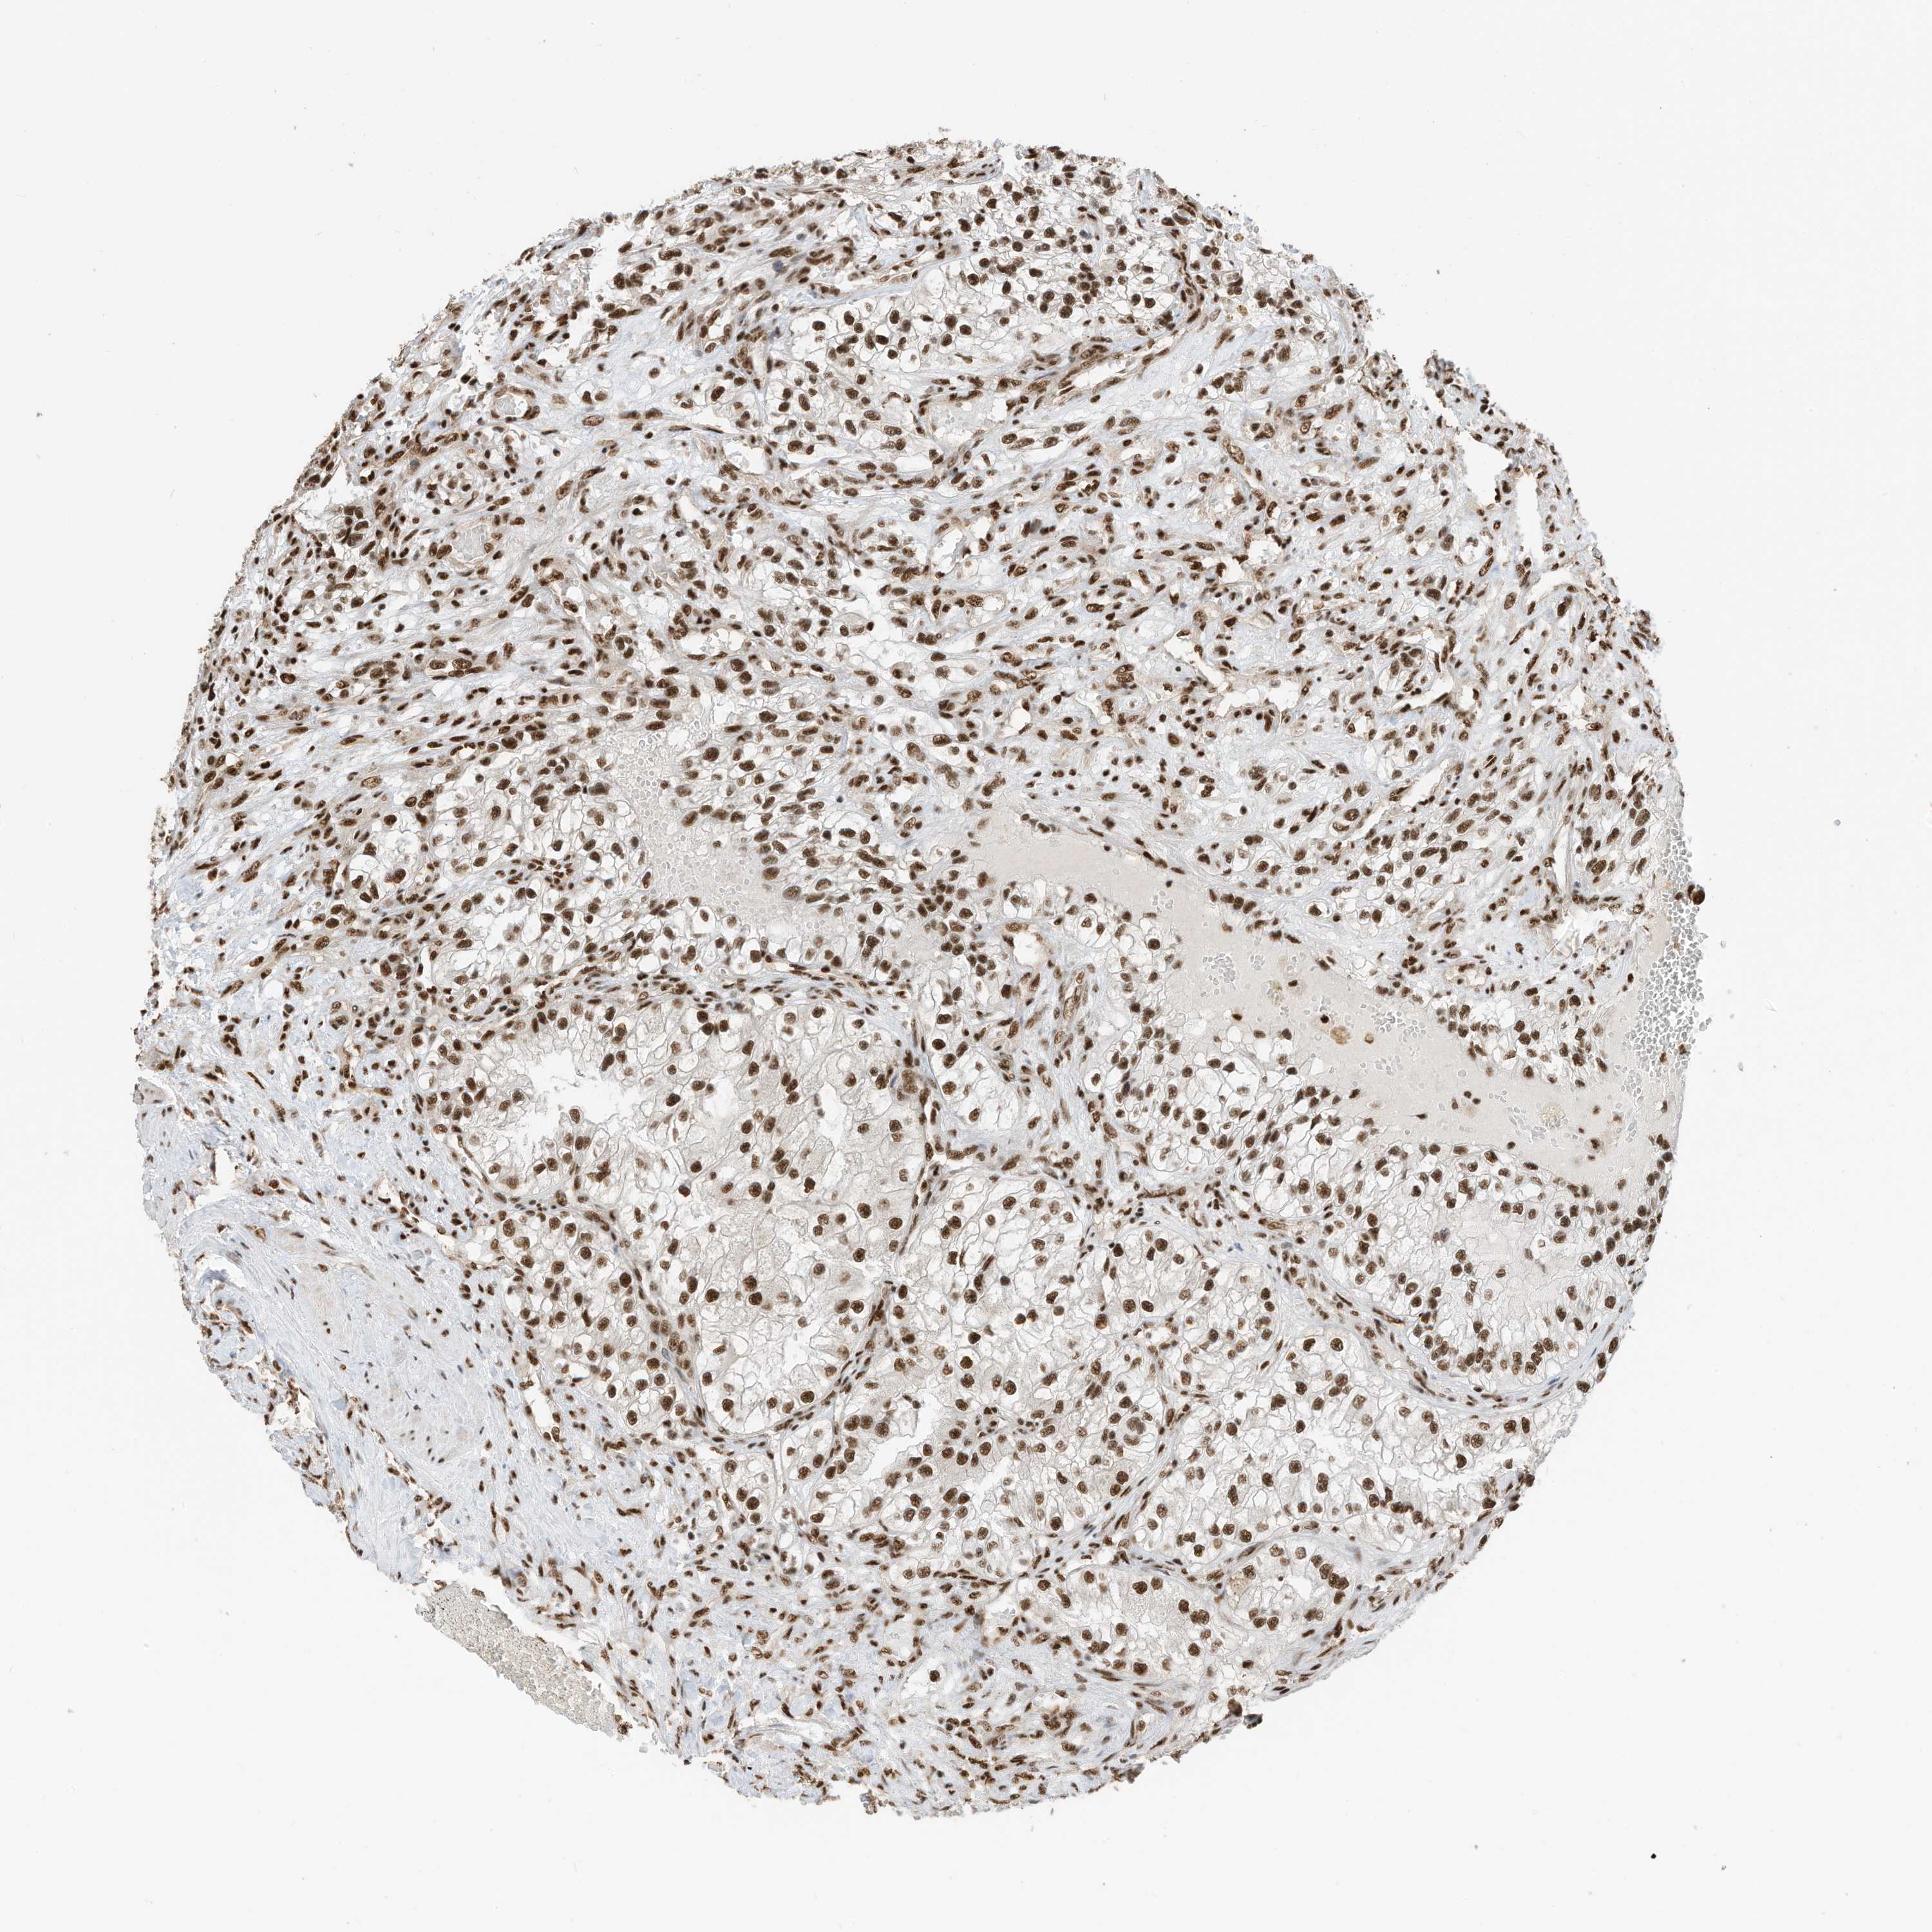

KIDNEY RENAL CLEAR CELL CARCINOMA (VALIDATION) - Interactive survival scatter ploti

The Survival Scatter plot shows the clinical status (i.e. dead or alive) for all individuals in the patient cohort, based on the same data that underlies the corresponding Kaplan-Meier plots. Patients that are alive at last time for follow-up are shown in blue and patients who have died during the study are shown in red.

The x-axis shows the expression levels (FPKM) of the investigated gene in the tumor tissue at the time of diagnosis. The y-axis shows the follow-up time after diagnosis (years). Both axes are complimented with kernel density curves demonstrating the data density over the axes. The top density plot shows the expression levels (FPKM) distribution among dead (red) and alive patients (blue). The right density plot shows the data density of the survived years of dead patients with high and low expression levels respectively, stratified using the cutoff indicated by the vertical dashed line through the Survival Scatter plot. This cutoff is automatically defined based on the FPKM cutoff that minimizes the p-score. The cutoff can be changed by dragging the vertical line or by entering a cutoff value in the square labeled "Current cut-off".

Under the Survival Scatter plot the p-score landscape (black curve; left axis) is shown together with dead median separation (red curve; right axis). Dead median separation is the difference in median mRNA expression between patients who have died with high and low expression, respectively. It is calculated as follows: median FPKM expression of dead patients with high expression - median FPKM expression of dead patients with low expression. This is intended to aid the user in visually exploring custom cutoffs and the associated p-scores and dead median separation.

Individual patient data is displayed and can be filtered by clicking on one or more of the category buttons on the top of the page. Categories describing expression level and patient information include: high, low, alive, dead, female, male and tumor stages. The scale of the x-axis can be toggled between linear and log-scale by clicking on the "x log" button. Mouse-over function shows TCGA ID, patient information and mRNA expression (FPKM) for each patient.

& Survival analysisi

Kaplan-Meier plots summarize results from analysis of correlation between mRNA expression level and patient survival. Patients were divided based on level of expression into one of the two groups "low" (under cut off) or "high" (over cut off). X-axis shows time for survival (years) and y-axis shows the probability of survival, where 1.0 corresponds to 100 percent.

SF3A3 is not prognostic in Kidney Renal Clear Cell Carcinoma (validation)

Best expression cut offi

: 37.08

P scorei

N/A

TCGA RNA samplesi

RNA-seq data is reported as average FPKM (number Fragments Per Kilobase of exon per Million reads), generated by the The Cancer Genome Atlas (TCGA) .

Normal distribution across the dataset is visualized with box plots, shown as median and 25th and 75th percentiles. Points are displayed as outliers if they are above or below 1.5 times the interquartile range. FPKM values of the individual samples are presented next to the box plot.

Average pTPM 35.4

Number of samples 100